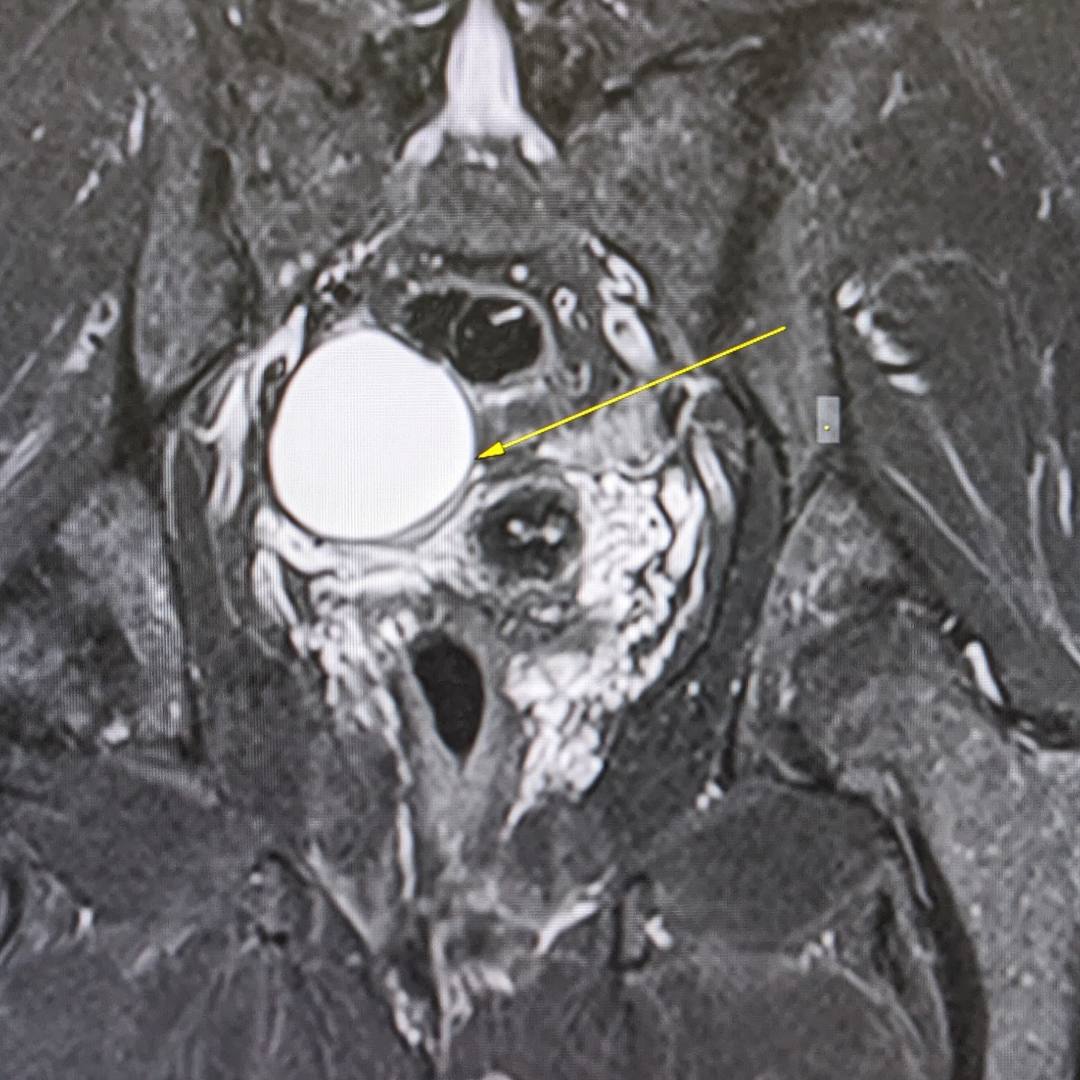

53-летняя пациентка обратилась к гинекологу в рамках программы check-up. При осмотре документации выяснилось, что на проведенных УЗИ-исследованиях от 2021 и 2023 года определяется образование правого яичника, требующее дифференциальной диагностики между эндометриоидной кистой и кистозно измененным яичником.

С целью оценки образования, уточнения его структуры и динамики роста пациентке было проведено МРТ органов малого таза.

При МРТ было выявлено жидкостное кистозное образование правого яичника без папиллярных разрастаний, гораздо больших размеров относительно первоначального УЗИ-исследования.

Учитывая анамнез пациентки, особенности структуры и размеры образования, была заподозрена цистаденома.